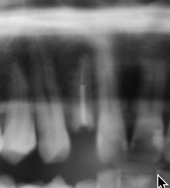

Hey Guys. I have an immediate implant for site #7 with a signif PARL, prob cystic. pt has no significant reported med hx. As this case approaches im asking myself weather physical debridments and pre/post op abx are enough to prevent infection/early failure. Thankfully in general after 8 years of placing implants ive only had a few of early implant failtures, with 90%+ being in immediate RCT sites. As I place an implant in this site this afternoon, im considering chemical irrigation of thr socket prior to osteomy with either Chlorhexine or Iodine. Do any of you use these routinely to irrigated infected sites, Or do you have a strong opinion for one or against another?